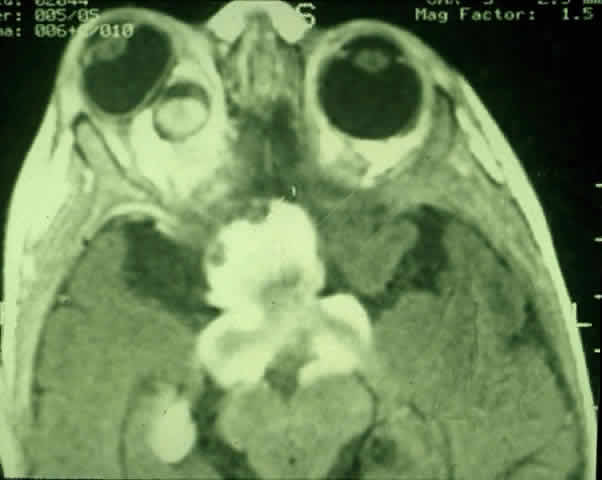

The use of chemotherapy for optic gliomas was prompted by the reported toxicity of radiation to the developing nervous system. Children irradiated before age 5 may have a tendency to incur behavioral and cognitive impairment.122 Results of chemotherapy for optic gliomas are difficult to interpret because of the sometimes indolent nature of these lesions, variably reported study follow-up periods, and small sample sizes. It does appear, however, that chemotherapy can effectively postpone radiation122 (Fig. 11 A and B). Unfortunately, there is little evidence that chemotherapy can provide long-term control of these tumors.20,122 In one series, approximately 60% of children treated for gliomas of the hypothalamus and optic pathways eventually had a relapse.122

Fig. 11. MRI scans demonstrating optic pathway glioma in a 14-month-old child with neurofibromatosis type 1, who presented with irritability and bilateral visual loss. The patient was treated with two courses of carboplatin and vincristine, resulting in marked visual recovery and a reduction in tumor size. Compare pretreatment MRI scan (A) with post-treatment MRI performed 5 months later (B). (Courtesy of Russell W. Walker, MD)